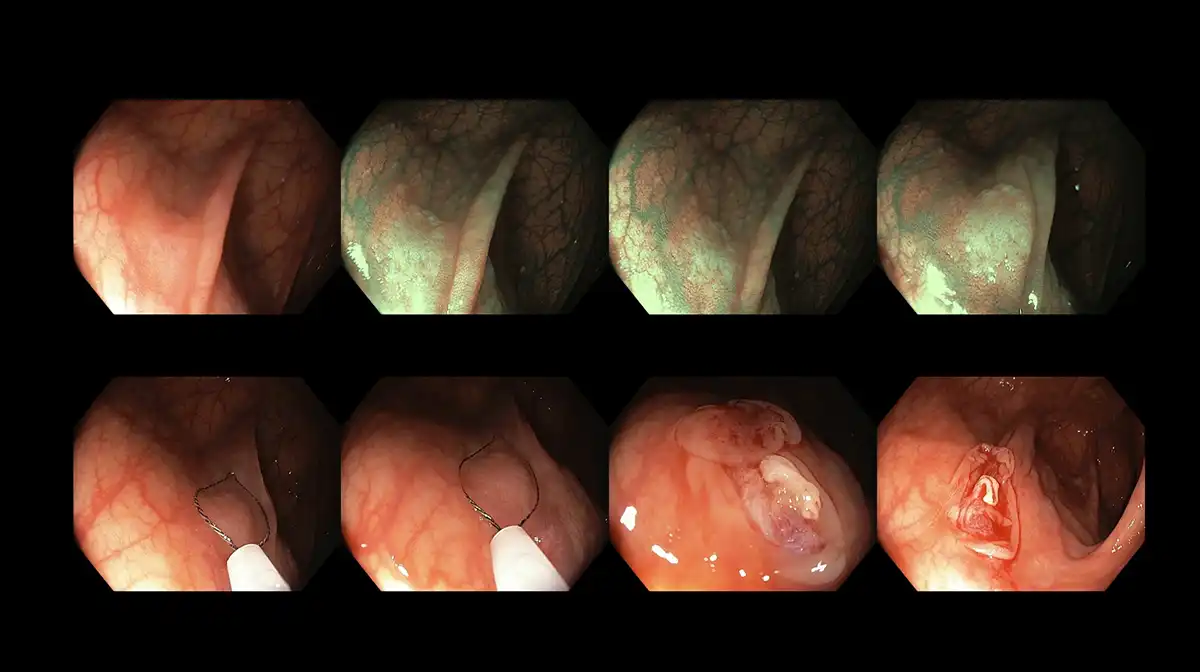

Fortunately, more than 90% of these polyps are small (less than 1 cm) and can be removed simultaneously during the colonoscopy by using a thin wire snare. Larger and more complex polyps, if detected early, may still be removed endoscopically in tertiary centers with expertise in advanced techniques such as endoscopic mucosal resection, endoscopic submucosal dissection, and full-thickness resection. However, invasive cancers often become friable and can lead to bleeding and mechanical obstruction, resulting in symptoms like lower gastrointestinal bleeding, constipation, changes in bowel habits, long-term loose stools, appetite loss, involuntary weight loss, ongoing abdominal discomfort, and a sensation of incomplete evacuation after defecation. By the time these symptoms appear, the likelihood of successfully removing polyps endoscopically decreases, as this treatment may not adequately cure the disease.

Once patients have adhered to all the instructions and see clear effluent in the toilet bowl, they are ready for the colonoscopy. Nurses will position the patient on their left side, place an oxygen cannula at their nostrils, and administer intravenous sedatives. The doctor will then insert the tip of the colonoscope into the rectum and navigate it through the colon, reaching the cecum and sometimes even the terminal ileum of the small bowel. As the doctor withdraws the colonoscope, the inspection begins, with a focus on identifying polyps and other potential pathologies. Thanks to advanced optics and evolving endoscopic technology, doctors can now utilize image-enhanced endoscopy techniques, such as the Olympus narrow-band imaging (NBI) or the Fujinon intelligent chromoendoscopy (FICE), to examine the surface and lining of the bowels, distinguishing normal from abnormal tissues, characterizing identified polyps, and assessing their grade and invasiveness to guide biopsies and resection options. Photographs and videos may be taken to assist in the final report.

Figure 13: Standardized classification used for polyp characterization to ascertain the type of polyps along with discerning the grade and invasiveness to determine resection modalities

Figure 14: Polyp characterization of a deep invasive cancer with image-enhanced endoscopy using the Olympus narrow-band imaging technology

Figure 15: Another example of characterization of an intermediately sized polyp with deep invasion which is not amenable for endoscopic removal